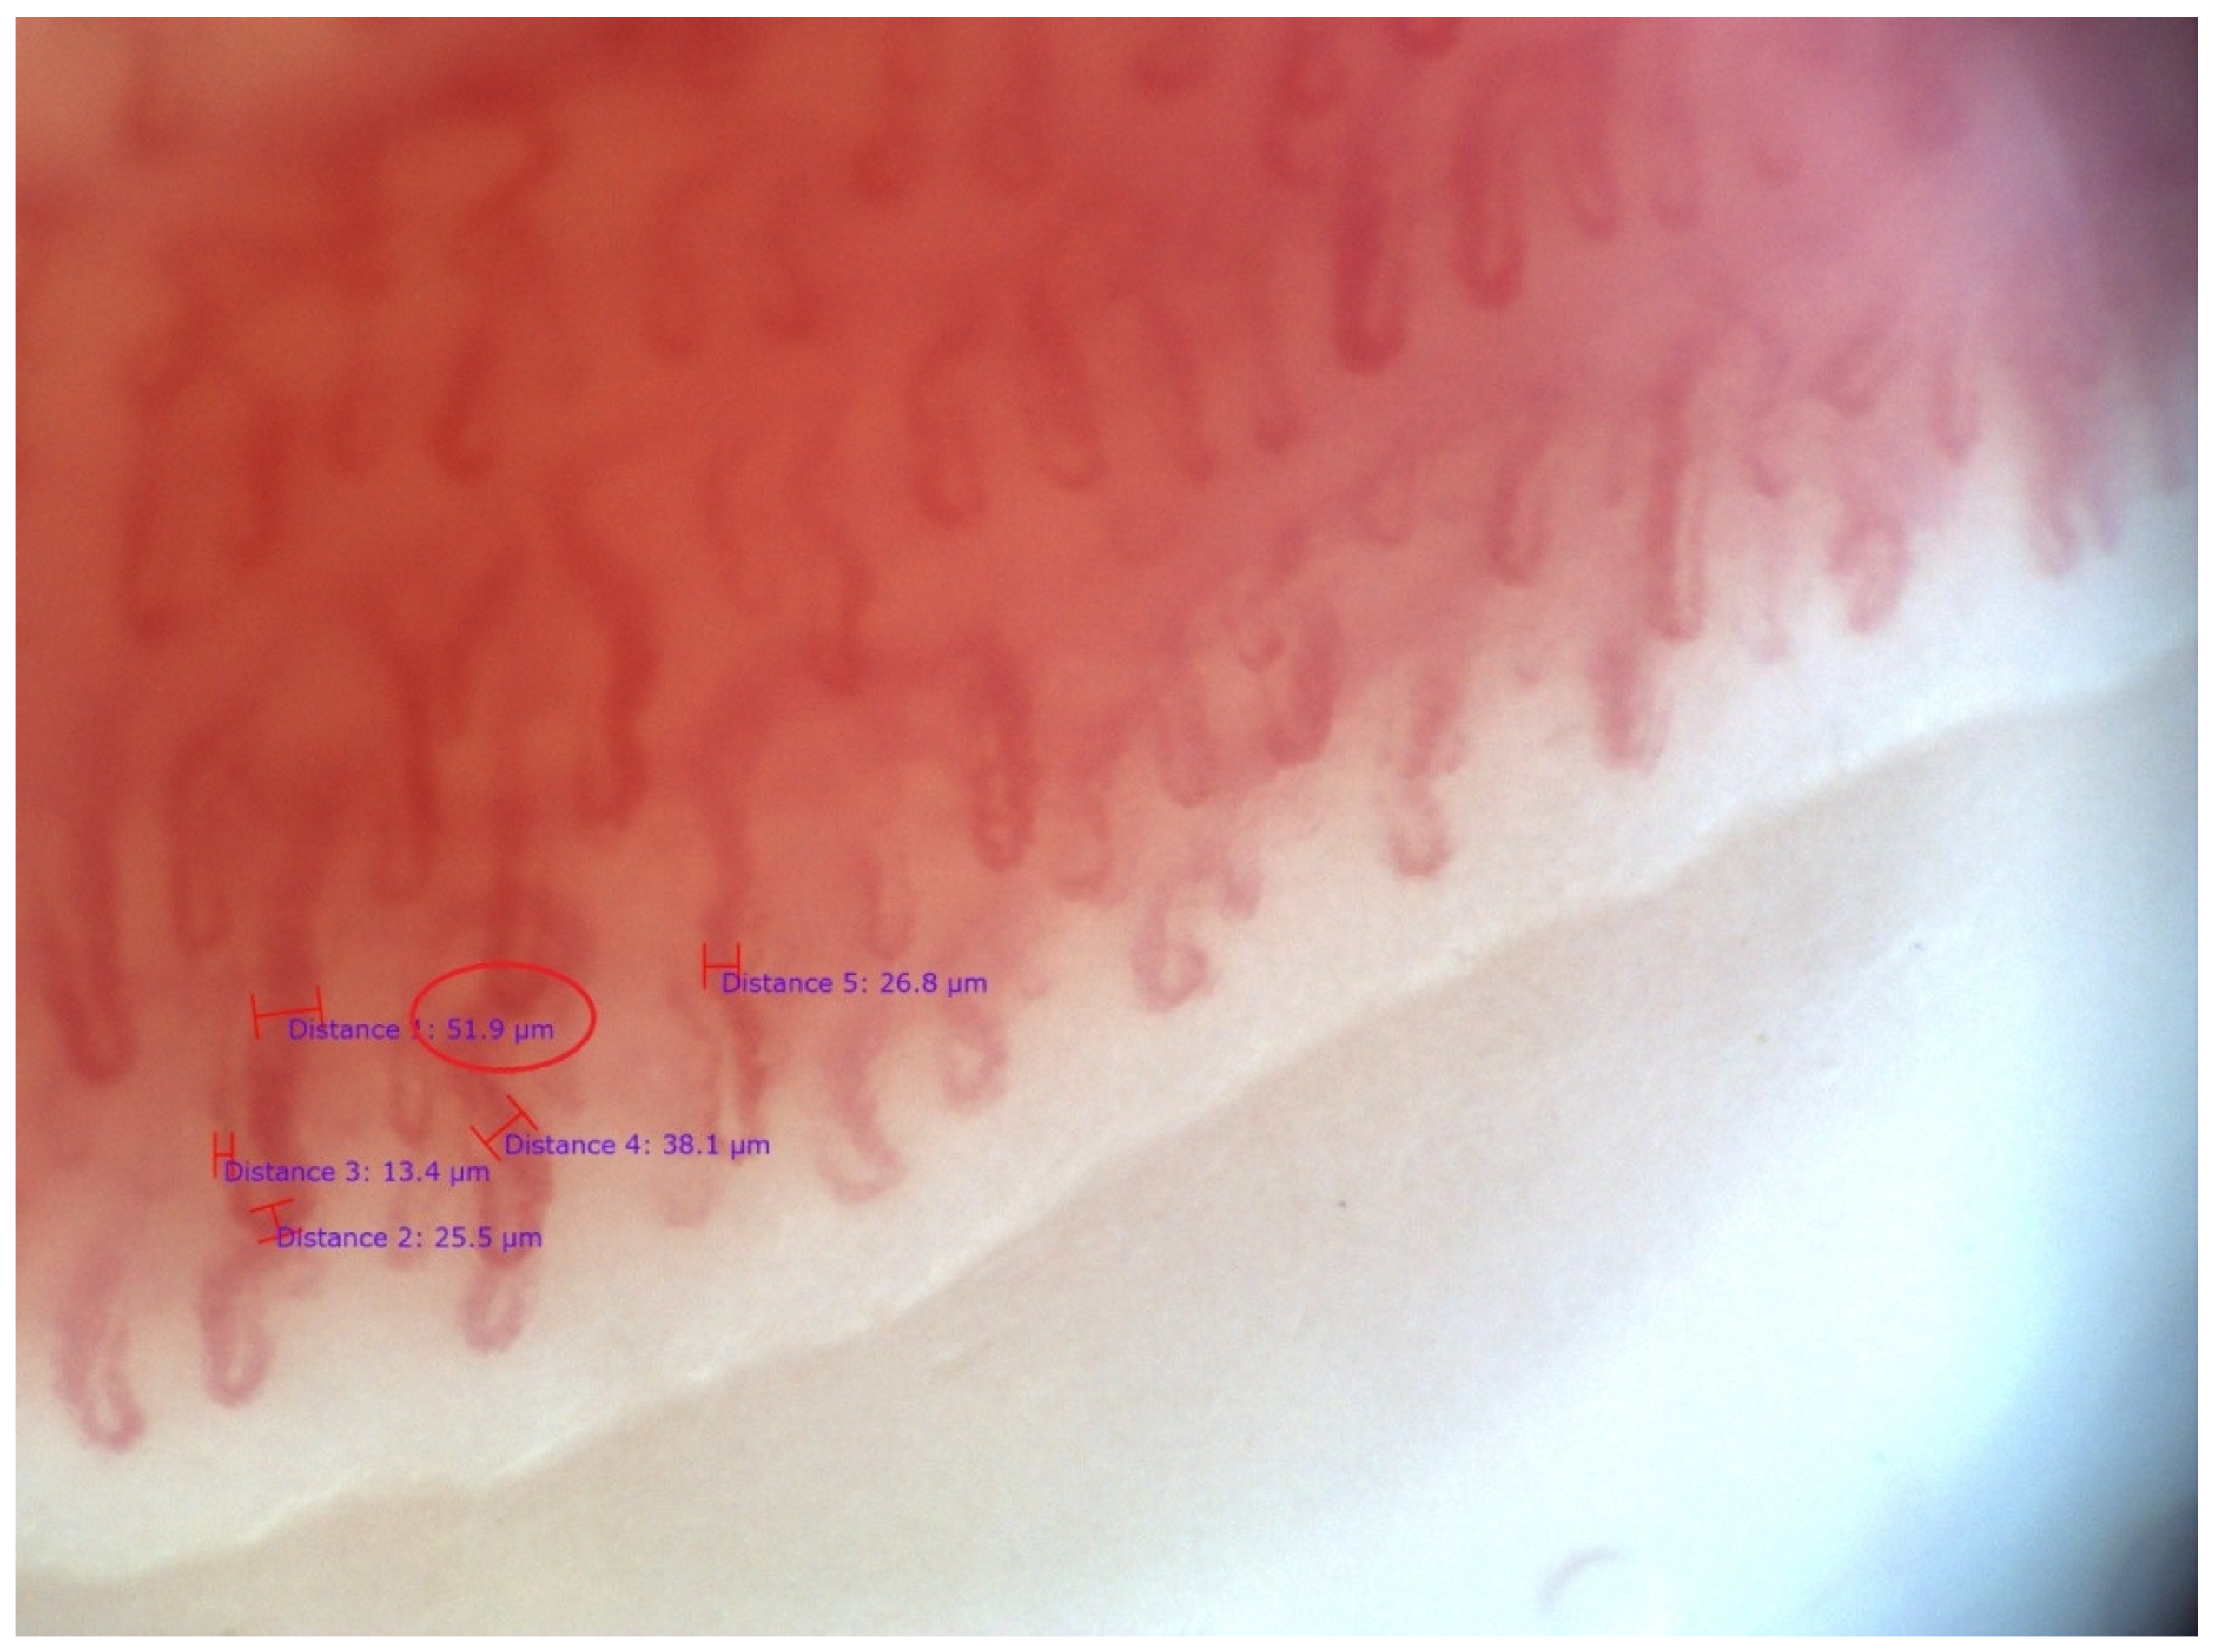

- Cutolo, M.; Sulli, A.; Pizzorni, C.; Accardo, S. Nailfold videocapillaroscopy assessment of microvascular damage in systemic sclerosis. J. Rheumatol. 2000, 27, 155–160. [Google Scholar]

- Lambova, S.N.; Muller-Ladner, U. Inhomogeneity of capillaroscopic findings in systemic sclerosis. Int. J. Rheum. Dis. 2019, 23, 207–215. [Google Scholar] [CrossRef] [PubMed]